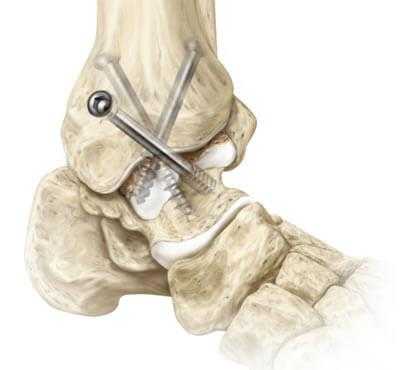

Обездвиживание достигается за счет жесткого соединения примыкающих концов костей сустава между собой специальными металлическими фиксаторами: спицами, винтами, штифтами. Это позволяет суставным поверхностям срастись друг с другом под нужным углом, то есть привести сочленение в полное неподвижное состояние, что снимает болевой синдром.

1. Внутрисуставный. Вскрытие капсулы сустава с последующим удалением поврежденного гиалинового хряща с поверхностей костных элементов. После репозиции костей в выгодном положении выполняется их фиксация металлическими приспособлениями.

- Внутрисуставный. В процессе хирургии выполняется вскрытие капсулы сустава с последующим удалением поврежденного гиалинового хряща с поверхностей костных элементов. После репозиции костей в выгодном положении выполняется их фиксация металлическими приспособлениями.